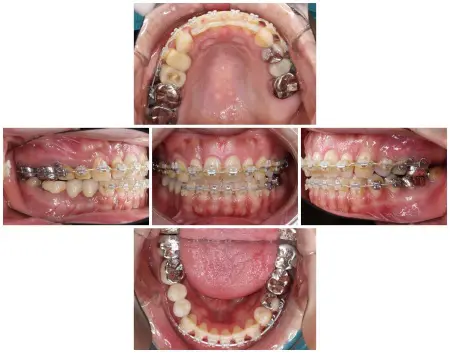

- 当院は、患者様の歯をできるだけ残し、長期的に再治療を防ぎ、質の高い健康を維持することを基本方針としています。

そのため「精密さ・耐久性・生体へのやさしさ」を重視した体制をとっており、原則として自由診療の治療をご提案しています。

一方、自由診療では個々の症例に合わせた治療設計、先進的な材料・技術の使用、再発予防を見据えた治療が可能です。